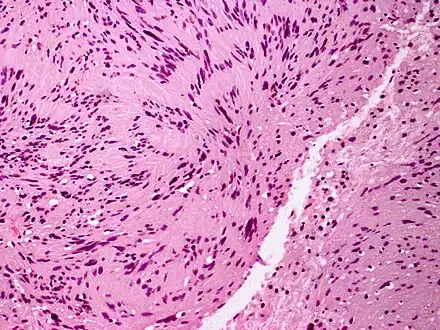

PEN is diagnosed by clinical recognition of the lesion and on subsequent histologic examination. Typically, the lesions are suspected to be schwannomas or neurofibromas clinically with PEN being an incidental finding on histology.[3]

PEN is typically diagnosed in patients between the ages of 40 and 60 years and occurs more frequently in females than males. The diagnosis of PEN may be difficult, even with confirmatory histology, due to its histological similarities with schwannomas and neurofibromas. It is imperative that the correct diagnosis is made the misdiagnosis of a neurofibroma may lead to unnecessary further investigation into associated systemic syndromes such as neurofibromatosis type 1 or multiple endocrine neoplasia syndrome.[3][4]

Palisaded and Encapsulated Neuroma